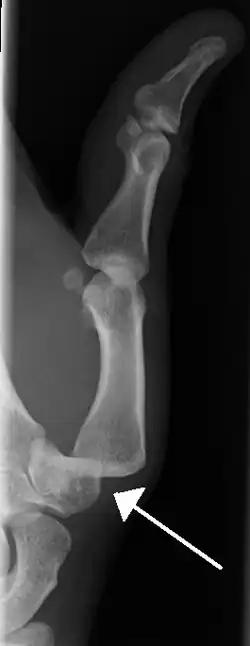

Radiograph of left index finger dislocation

Dislocation of the carpo-metacarpal joint.